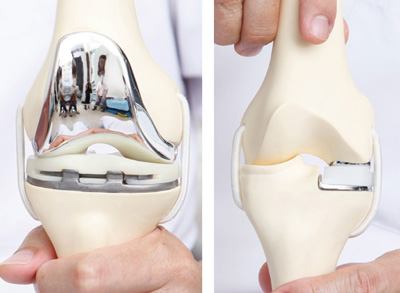

人工膝関節(全置換と部分置換)の一例

人工関節の手術は、膝関節の表面全てを人工の関節に置き換える全置換術(ぜんちかんじゅつ)と、主に内側のみを換える部分置換術(ぶぶんちかんじゅつ)があります。痛みが強く、変形が全体に及んでいる時は、全置換術が適応となります。部分置換術は、膝の内側だけに傷みがある「変形性膝関節症」や、大腿骨内顆骨壊死などで行われる手術ですが、全置換術と比べ手術の傷を小さくでき、靭帯などを温存できるので膝の可動域がよいのがメリットです。しかし、「変形性膝関節症」を長年我慢され、症状が進行してから手術を選択される方は、一般的には全置換術で行う場合が多いです。